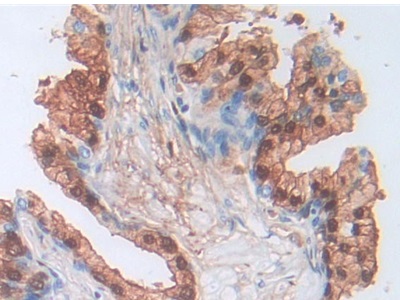

The antibody is a rabbit polyclonal antibody raised against SCAF11. It has been selected for its ability to recognize SCAF11 in immunohistochemical staining and western blotting.

Immunohistochemistry in paraffin section: 5-20ug/ml